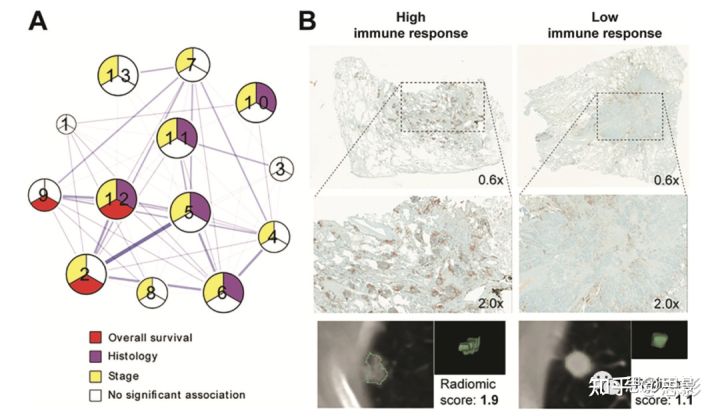

图3,影像组学数据和基因通路数据之间的关联可以从组织学上探索。

A、该图描述了Grossman等人提出的通路富集和影像组学特征之间的相关性分析。多个簇(数字1-13)描述了不同生物过程和图像信息之间的关系。进一步将相关影像组学特征与免疫组织化学染色(核CD3表达)进行相关性研究,以验证研究结果,并为了解肿瘤遗传学和影像学特征之间的相互作用提供联系。B、显示了免疫反应强和/或影像组学评分高(左)和免疫反应低和/或影像组学评分低(右)的肿瘤示例。

非小细胞肺癌中的表皮生长因子受体状态是一个广泛研究的课题,因为其发生频率高,而且这种突变可用酪氨酸激酶抑制剂治疗(33,34)。多项研究报告了与遗传检测确定的表皮生长因子受体突变状态相关的CT特征。然而,正如Yip等人(35)所指出的,其中许多人得出了相互矛盾的结论(36-38),这破坏了该方法的再现性。将基因组相关性与组织学分析提供的其他生物学指标相结合,可能证明有必要最终验证这些不一致的发现。在遵循这些原则的一项研究中,Sun等人(39)开发了免疫浸润的影像组学特征,将得分与相关基因表达组、病理结果和生存数据相关联。同样,同样,Tunali等人(40)证明,根据遗传图谱和免疫组织化学(IHC),能预测免疫治疗后生存率的CT影像组学特征也与缺氧密切相关。Mu等人基于PET/CT影像组学研究程序性死亡配体1或PD-L1状态和表皮生长因子受体突变状态的预测因子。当这两种表型结合在一起时,它们产生了一个强大的决策支持工具,因为这两种表型通常是相互排斥的。除了额外的验证之外,这些研究中的多重相关因素的组合还揭示了影像组学特征关系的生物学驱动力。Beig等人(43)利用癌症中氧合状态的已知相关性,通过患者MRI扫描发现与肿瘤缺氧相关的影像组学特征,并随后显示其与胶质母细胞瘤患者的生存密切相关。Grossman等人(44)提出了一种替代方法,旨在揭示影像组学特征和通路信息之间的关系。使用双聚类方法来确定与结果相关的影像基因组相关性集群,随后验证这些集群,以显示与免疫浸润或核因子kB或NF-kB表达(也参与免疫反应)的相关性,以及与靶向靶向IHC的相关性(图3)。组织学信息的引入可以提供必要的联系,以了解遗传学和描述宏观肿瘤纹理的影像组学特征之间的关系。